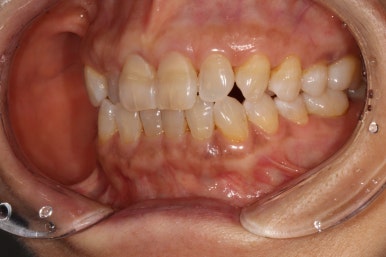

40대 남자 환자분이었습니다. 왼쪽 아래 맨 뒤 어금니의 불편감을 호소하시고 계셨습니다.

앞니의 치경부 마모가 눈에 띄긴 하지만, 전체적으로 쌓여있는 치석말고는 별 문제가 없었습니다.

화살표로 가리치고 있는 치아의 불편감을 호소하고 계셨습니다.